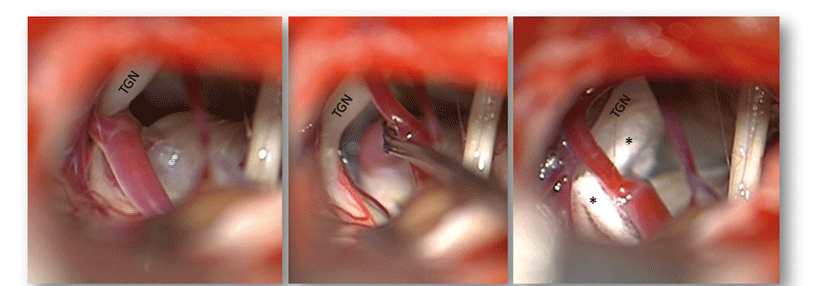

Trigeminusneuralgien machen ein Drittel der Fälle von Gesichtsschmerzen aus. Fast genauso oft steckt ein Clusterkopfschmerz dahinter, und bei etwa jedem zehnten Patienten eine postherpetische Neuralgie oder ein atypischer idiopathischer Gesichtsschmerz. Die Schmerzcharakteristik (s. Kasten), mögliche Trigger und Begleit­erkrankungen müssen daher genau erfragt werden, betonte Privatdozent Dr. Tim ­Jürgens von der Klinik für Neurologie an der Universitäts­medizin Rostock.